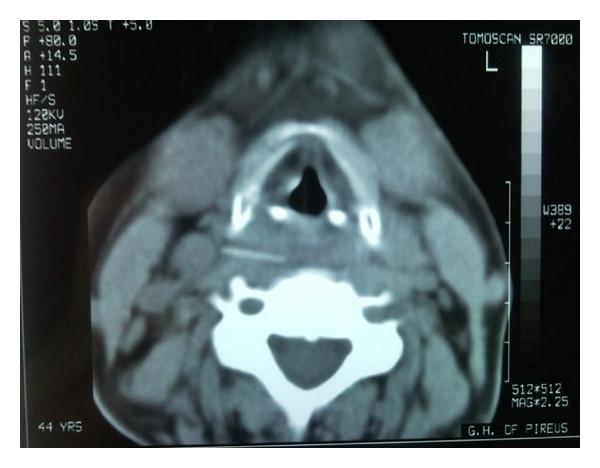

Impaction of foreign bodies in the upper aerodigestive tract is commonly encountered in ENT practice. The present paper describes an iatrogenic complication with migration of an impacted foreign body (chicken bone) of the hypopharynx into the prevertebral space, after unsuccessful attempt of endoscopic removal. The foreign body was visualized with cervical CT scan lying extraluminally between the major vessels of the neck. An open surgical procedure with neck exploration was necessary for the definite treatment.

上气道消化道异物嵌顿在耳鼻喉科临床实践中较为常见。本文描述了1例医源性并发症,下咽嵌顿异物(鸡骨)在内镜取出失败后迁移至椎前间隙。颈椎CT扫描显示异物位于颈部大血管之间的管腔外。明确治疗需要行颈部探查的开放性手术。